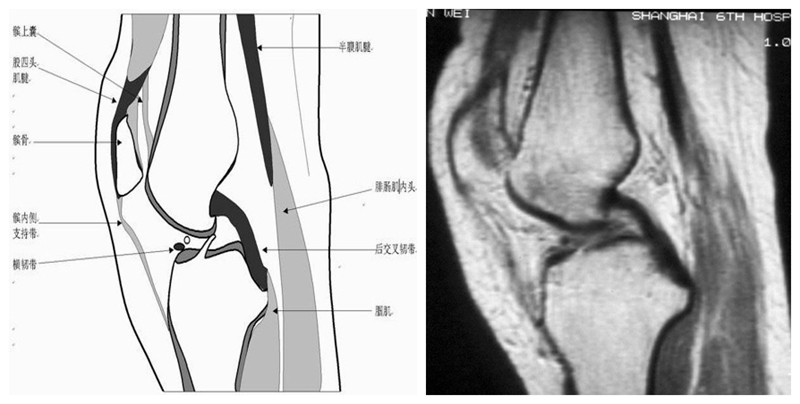

膝关节冠状面MRI解剖

显示内外侧副韧带、腘肌和拱状韧带,有无信号和结构改变,侧重关节胫股软骨的两边和半月板的体部。

冠状位解剖第一层

冠状位解剖第二层